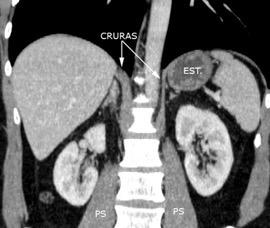

Parte lumbar: 1.Ligamentos arcuatos medial y lateral

2. Cruras conectadas a vértebras lumbares y discos. L1-3 a la dcha. L1-2 a la izda.

Cruras conectadas por encima del tronco celíaco por ligamento fibroso arcuato medial. Panicek DM et al. Radiographics. 1998

Las fibras más bajas de las cruras se funden con las de las vainas de los músculos psoas, acotando un espacio llamado “Espacio abierto de la vaina del psoas”, que comunica las cavidades torácica y abdominal.

Panda A et al. “Straddling Across Boundaries”. Thoracoabdominal Lesions: Spectrum and Pattern Approach. Curr Probl Diagn Radiol, 2015 /Restrepo CS et al. The diaphragmatic crura and retrocrural space: normal imaging appearance, variants, and pathologic conditions. Radiographics 2008